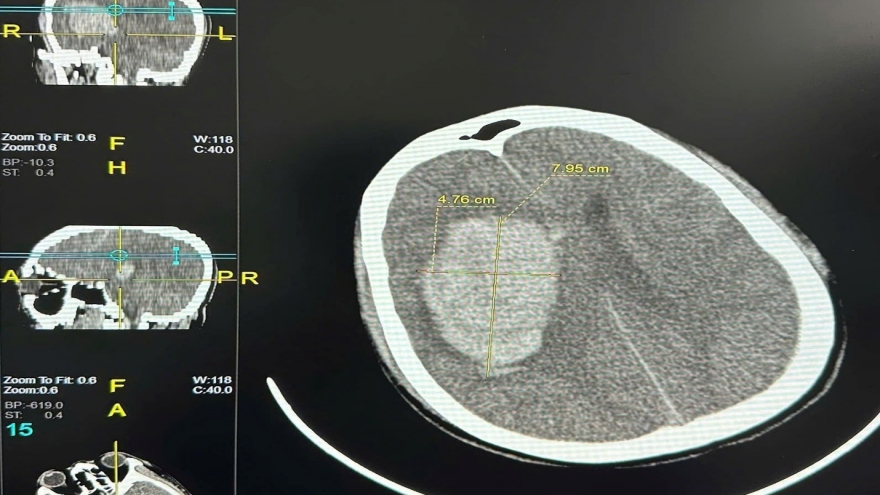

VOV.VN - Thời tiết chuyển lạnh khiến nhiều người cao tuổi phải nhập viện vì viêm phổi, tim mạch hoặc tai biến. Ở tuổi xế chiều, sức đề kháng suy giảm khiến họ dễ bị tác động bởi thay đổi nhiệt độ. Các bác sĩ khuyến cáo, cần giữ ấm và phòng bệnh chủ động để tránh biến chứng nguy hiểm.